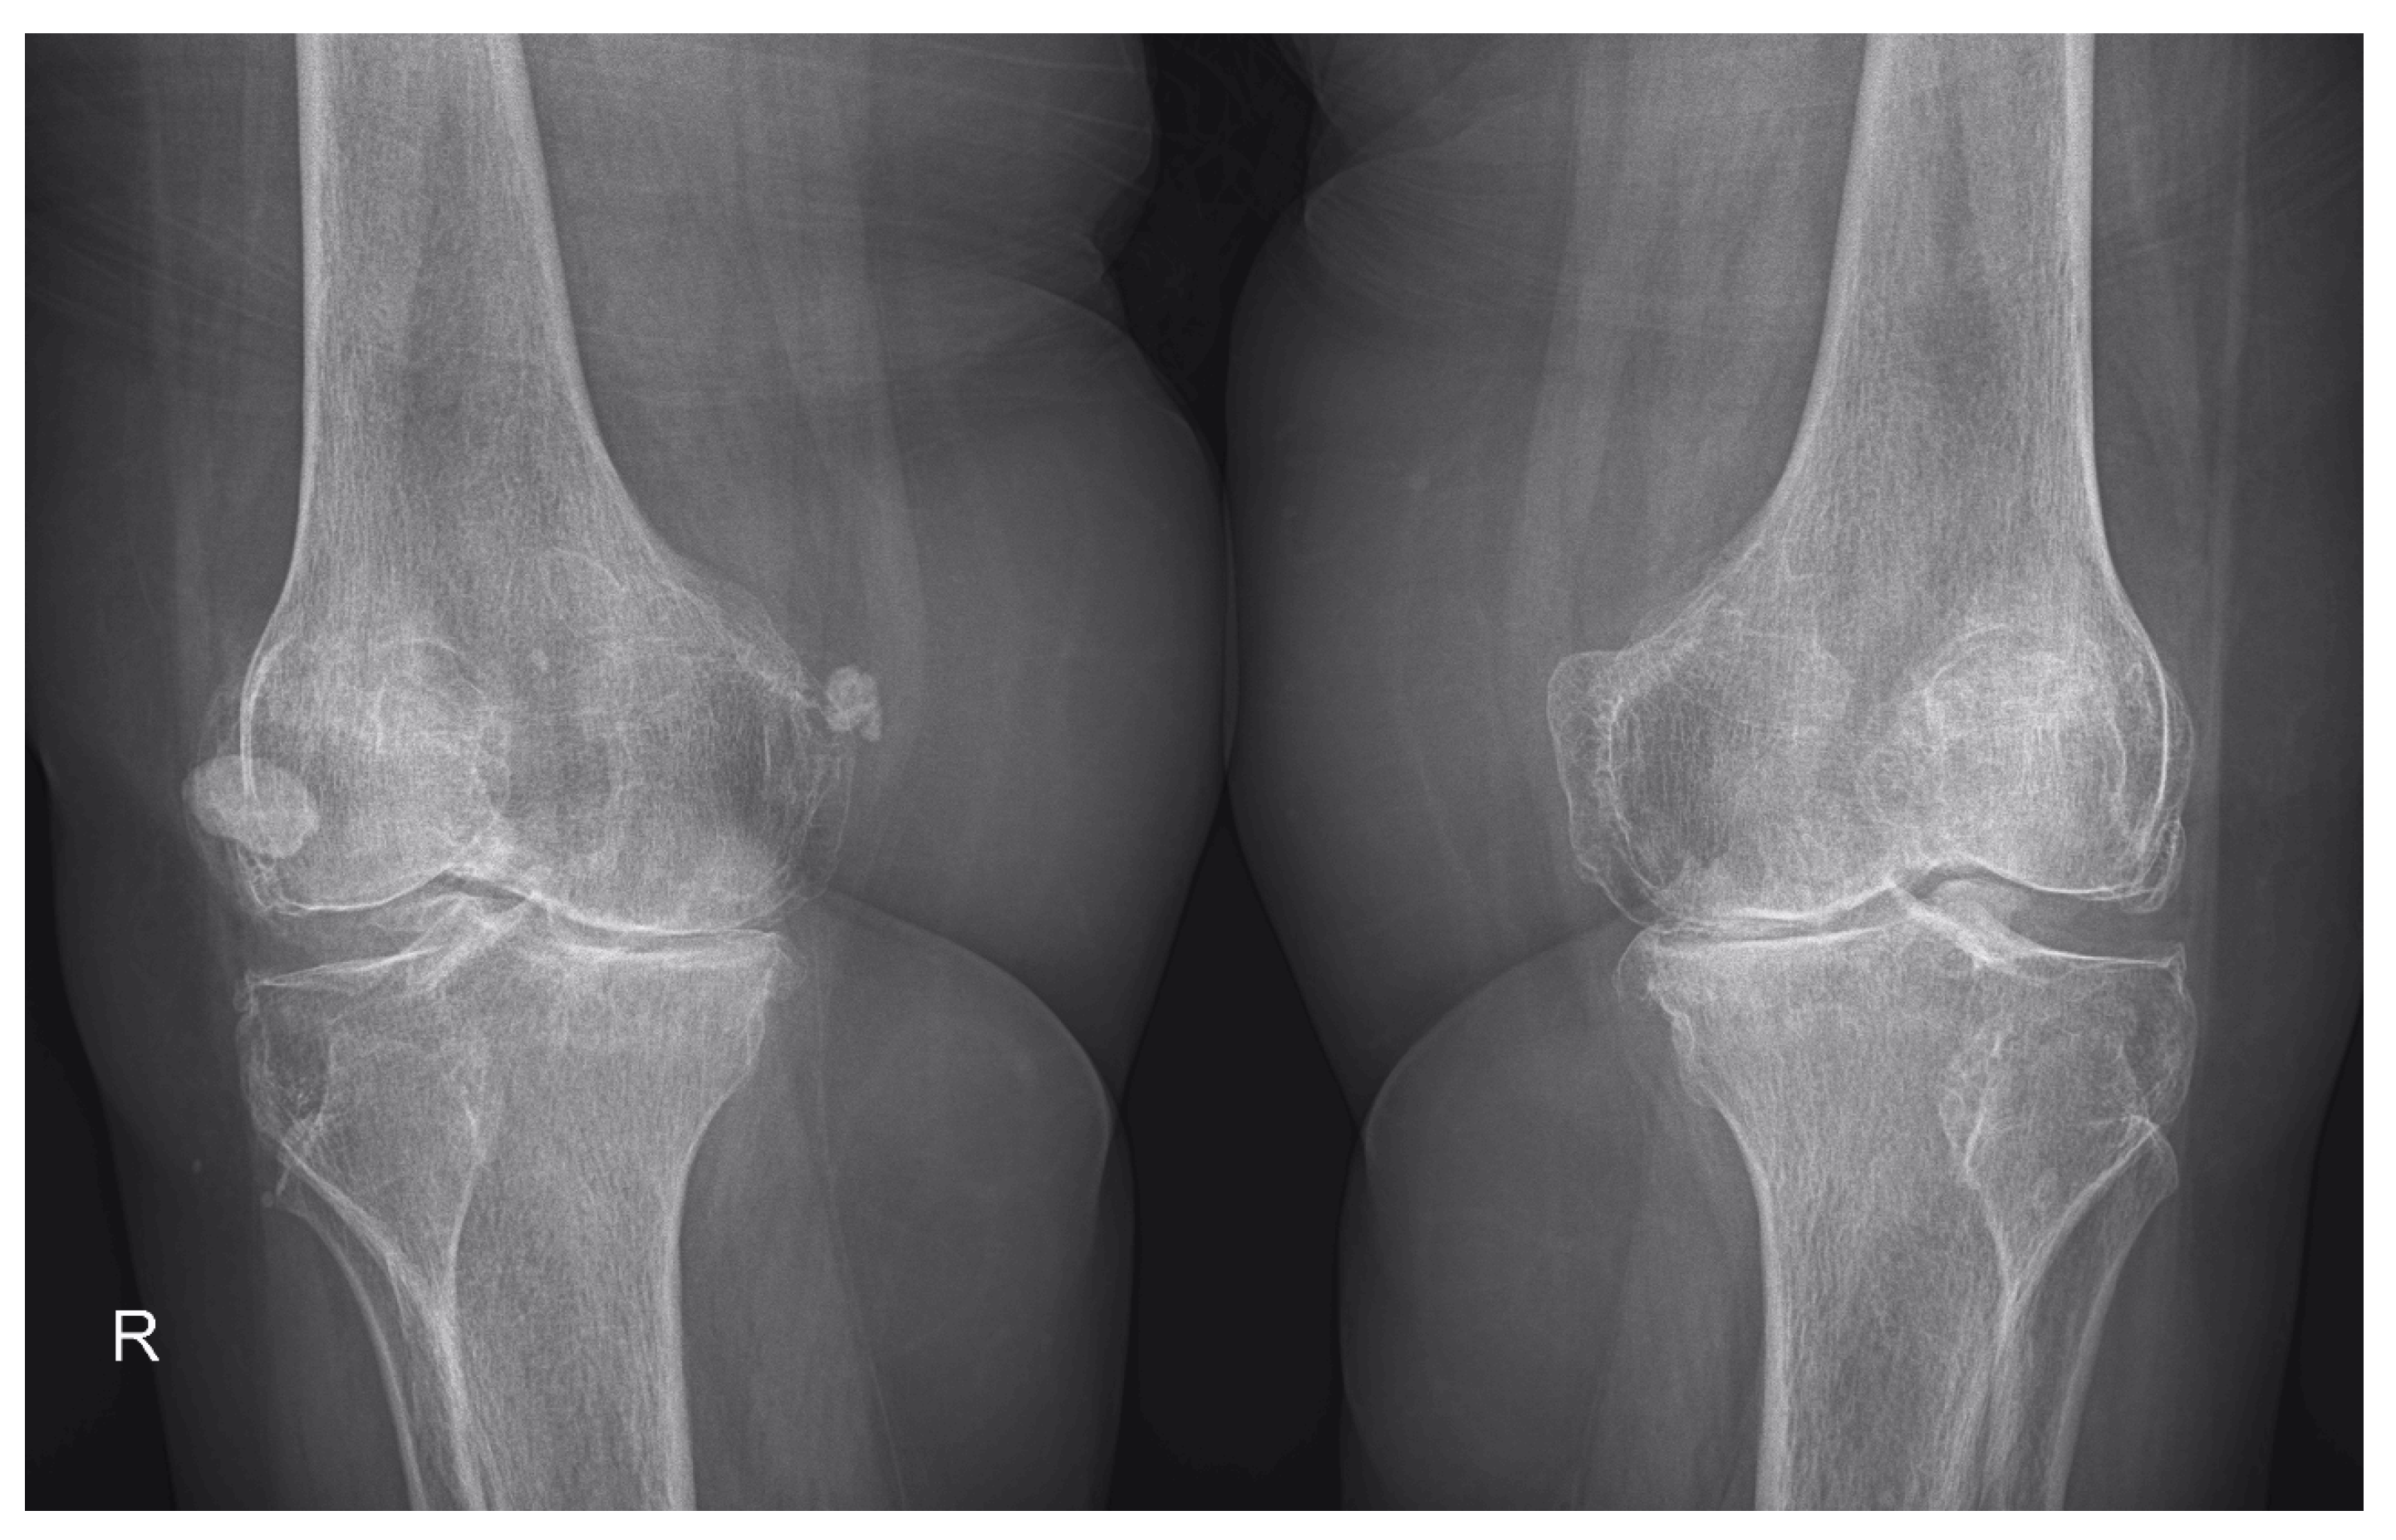

2.2. Demographic Characteristics and Assessment of Clinical, Laboratory and Imaging Data